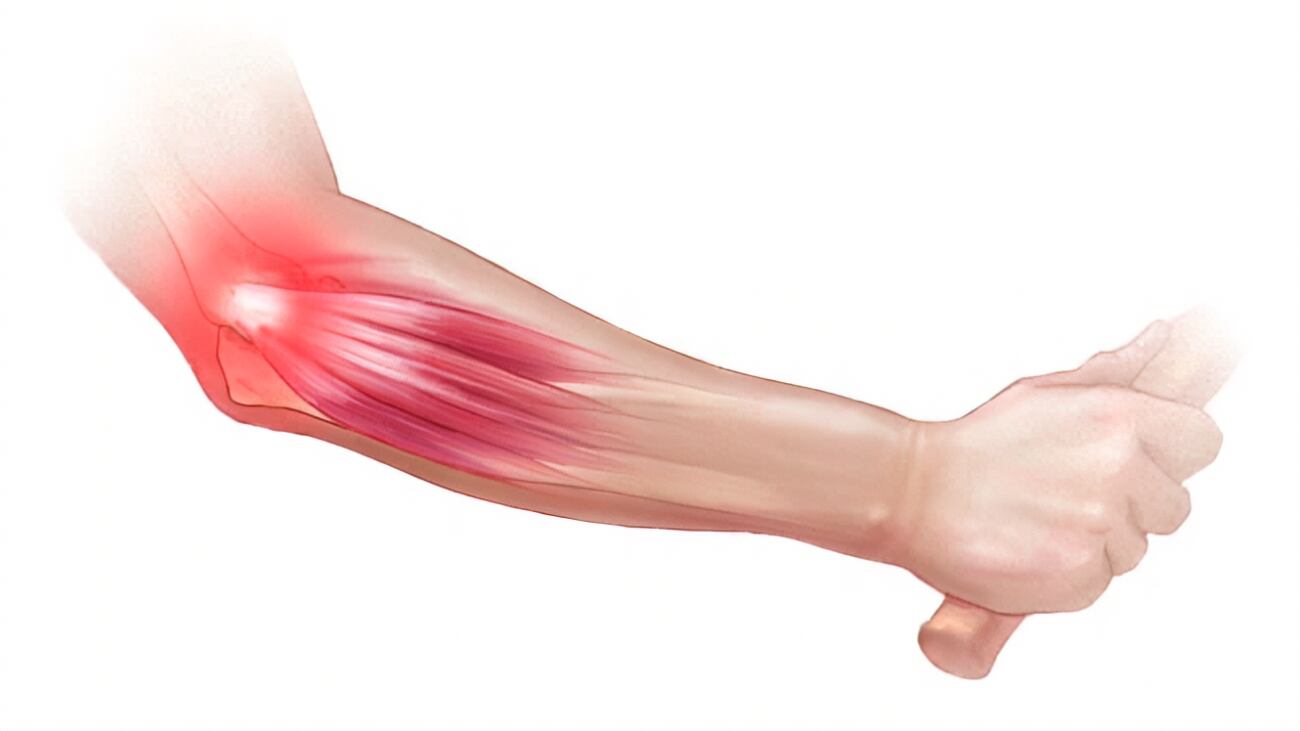

En función de lo expuesto por Mayo Clinic, “el codo del tenista (epicondilitis lateral) es una afección dolorosa que ocurre cuando los tendones del codo se sobrecargan, frecuentemente por movimientos repetitivos de la muñeca y el brazo”.

“El dolor del codo del tenista se manifiesta principalmente en el lugar donde los tendones de los músculos del antebrazo se unen a la protuberancia ósea en el exterior del codo. El dolor también se puede propagar al antebrazo y la muñeca”, acotan en el mencionado sitio web.